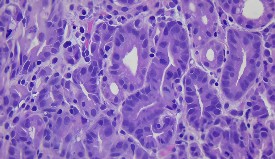

En el control endoscópico de junio del año 2023, se objetivó a nivel del tercio distal del cuerpo gástrico, en la cara posterior, una lesión de 30 mm, de bordes elevados, congestivos, con un área de depresión central (Figura 1). Se le practicó una biopsia, con resultado de presencia de metaplasia intestinal incompleta (en el 20 %) y atrofia. Ante los hallazgos, se decidió realizar una nueva endoscopía con cromoendoscopía en octubre del 2023, y se evidenció la lesión descrita previamente, que a la instilación con ácido acético mostró una reacción positiva a nivel de depresión. Se tomó otra biopsia, con resultado de adenocarcinoma tubular infiltrante moderadamente diferenciado (Figura 2).

Figura 2 Biopsia de lesión gástrica, diagnóstico microscópico (parafina). Adenocarcinoma tubular infiltrante moderadamente diferenciado.